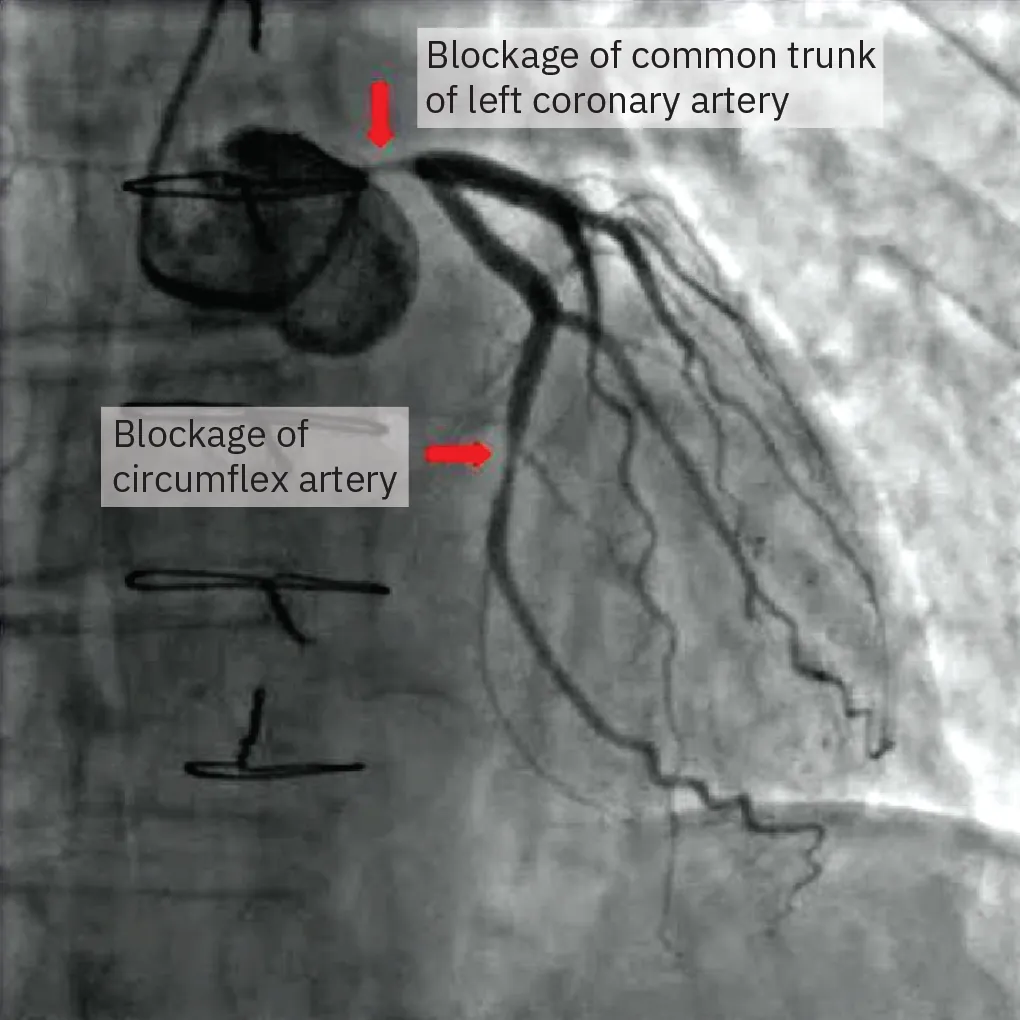

Figure 22.3 shows an occlusion in the circumflex artery and the common trunk of the left coronary artery. Occlusion in the circumflex artery can lead to ischemia and possible infarction in the apex of the heart.

An x ray shows blockage in the left coronary artery and the circumflex artery.

Figure 22.3 This coronary angiogram (a type of x-ray) shows a stenosis (blockage) in two different arteries. (credit: modification of work by Pantaleo, M.A., Mandrioli, A., Saponara, M. et al. “Development of coronary artery stenosis in a patient with metastatic renal cell carcinoma treated with sorafenib.” BMC Cancer 12, 231 [2012]. https://doi.org/10.1186/1471-2407-12-231; CC BY 2.0)